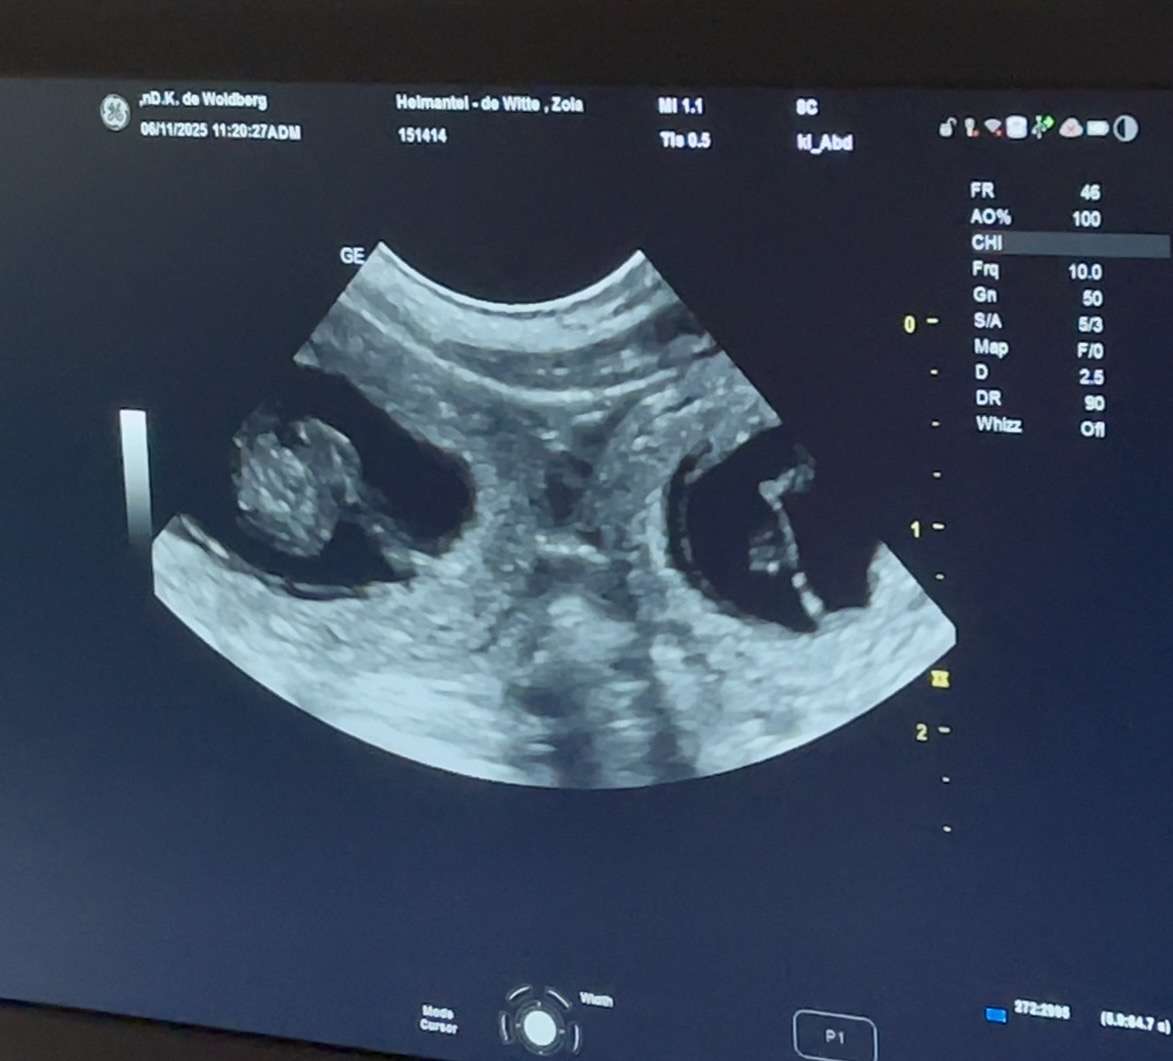

06-11-2025; Super goed nieuws want vandaag hadden we een prachtige echo met Zola!! Ze is drachtig en we verwachten rond 12-12 weer basenji puppies🤩